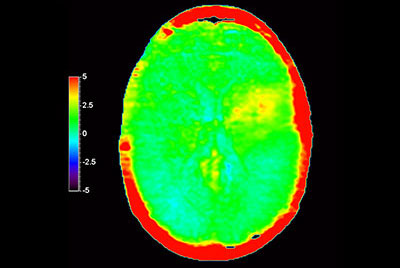

3D APT brain imaging for glioblastoma recurrence

-

Brain astrocytoma post radiotherapy, incl. 3D APT

-

Brain with glioblastoma, incl. 3D APT

-

Brain lesion with 3D APT

-